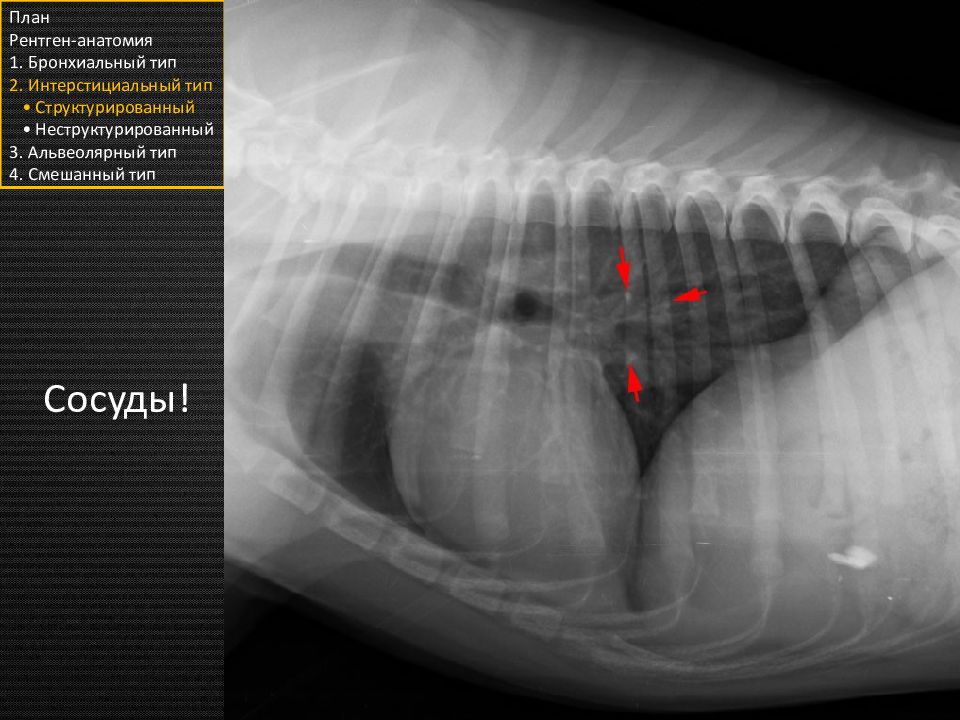

Слайд 27

План Рентген-анатомия 1. Бронхиальный тип 2. Интерстициальный тип • Структурированный • Неструктурированный 3. Альвеолярный тип 4. Смешанный тип Сосуды!